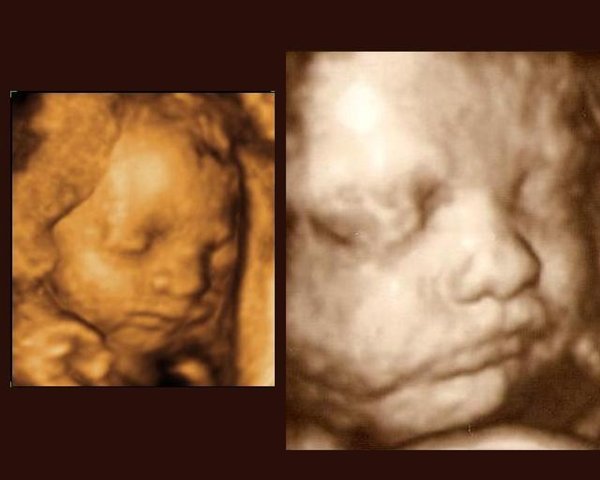

Til venstre ses lillesøster (Celina) i uge 27+3

Til højre på billederne er det storesøster (Bianca) i uge 29+3